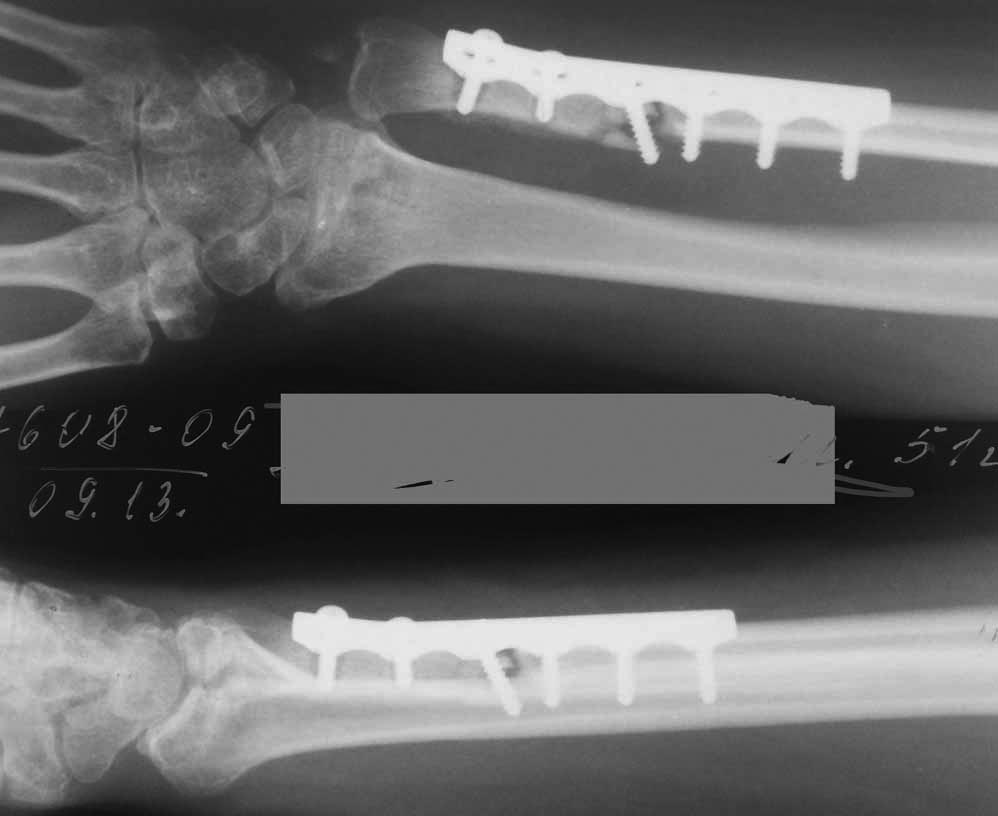

[Ortho] Последствия травмы и лечения перелома предплечья

Оказывается, забыл вопрос сформулировать. :) Изначально рассматривались:

- корригирующая укорачивающая остеотомия лучевой кости из ладонного

доступа с накостной фиксацией.

- миниинвазивное удаление пластины с локтевой кости, и ее штифтование с

восстановлением анатомии радиоульнарного сочленения (риммирование можно

рассматривать как своеобразную костную пластику). Будет ли это достаточным?

Имя     : Xr forearm dam.jpg